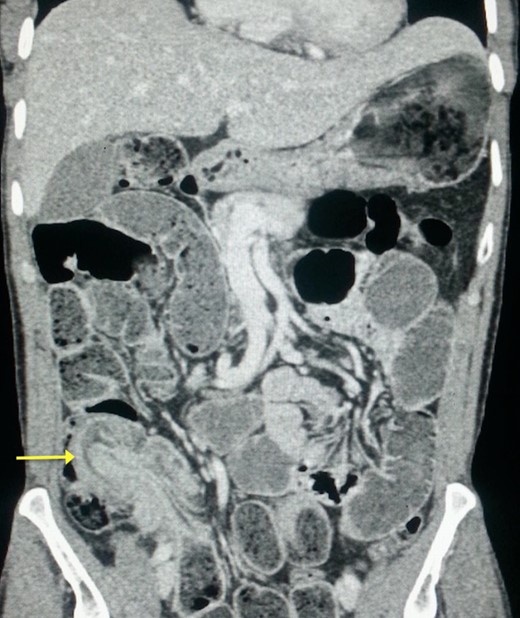

Upon laparotomy, we found an ileocecal intussusception, with mesenteric lymphadenopathies and a dilation of the whole small bowel (Fig. 3). We performed a right hemicolectomy, without attempting to reduce the intussusception, and an end-to-end ileotransverse anastomosis.